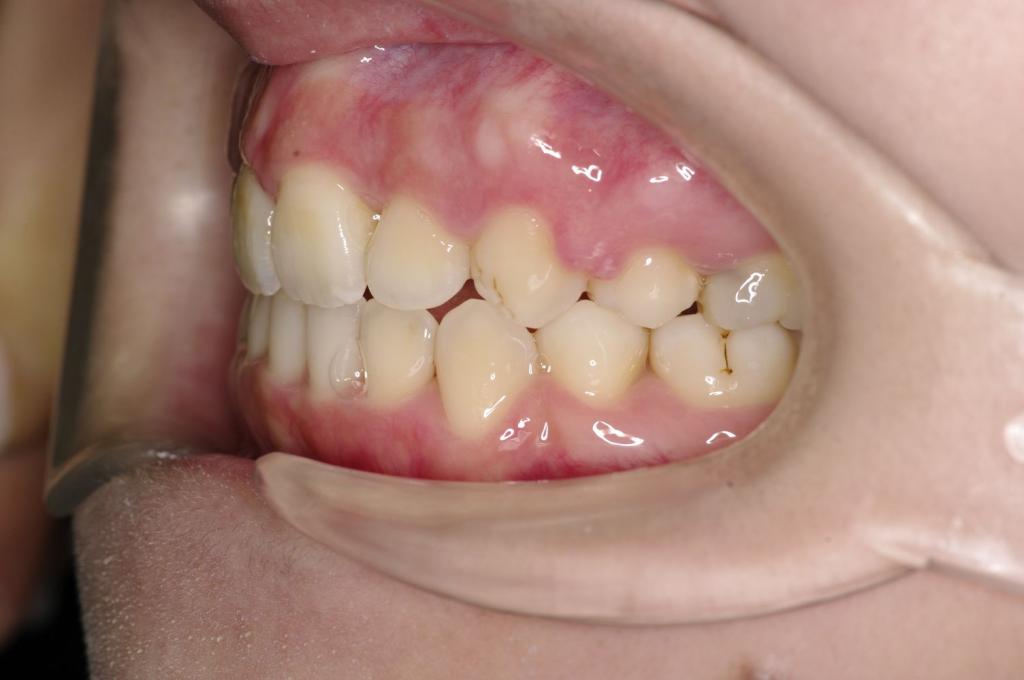

前歯、出っ歯・開咬の矯正治療

(治療期間、治療前後写真、治療方法、費用)WORKS